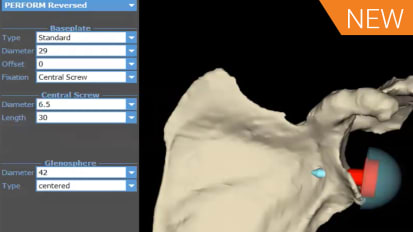

SKU: 014240A

We're very pleased to have Dr James Gregory with us tonight. Dr. Gregory attended Medical School of the University of Pennsylvania and his orthopedic residency at Rush University Medical Center. Dr. Gregory completed his shoulder fellowship at Washington University School of Medicine and is currently an assistant professor in the Department of Orthopedic surgery of McGovern Medical School at the University of Texas Health Science Center at Houston. Also with us tonight is our esteemed faculty panel, Dr George Athol, Dr J. Keener and Dr Robert Tashjian. Dr Atthe Walls, a professor of surgery at the University of Western Ontario, handed Upper Limb Center and ST Joseph's Healthcare. Dr. Athol is also a clinician scientist at Lost in Health Research Institute program of Advanced Surgical Technologies. Dr. Keener is a professor in chief of orthopedics and fellowship director of the shoulder and elbow service at Washington University Department of Orthopedic Surgery in ST Louis, Missouri. And Dr Tash is professor of orthopedics vice chairman for research at a secular donkey and junior presidential endowed professor at the University of Utah School of Medicine and Salt Lake City, Utah. And finally, we're extremely honored to have a special guest Panelist with us tonight. I'd like to turn it over to Dr Keener for that introduction. Thank you, Tim. This is our fourth and final installment, and we've saved a very tough topic for the last, uh, last session. This is Revision Illinois. We're very pleased to have Dr Javier Darryl Day. Uh, join us today. Thank you very much, Javier. Er, um, for those of you in the shoulder world, Javier needs no introduction. He's, uh, been a practicing Children. Although specialists in Atlanta for several decades. Uh, that doesn't mean he's old. That just means he's experience. And he knows what he's doing. Javier is very well trained, and he completed the Columbia Fellowship back when Dr Near was still a teaching. So hey, we are looking forward to hearing his opinions and him sharing his knowledge from his extensive experience. And we really couldn't have a better, uh, guest speaker or faculty for this last topic. So thank you. Have a year for joining us today. So with that, we're gonna have James kick off with his slides, right? You want circle kind of police, Pierre. Okay. So I appreciate the opportunity to talk with everybody today, and I put together four cases that I hopefully think will cover a variety of different spectrum of revision gonna pathology. And I'm honored to be here with the sustained, distinguished Panelists and hope people take a little easy on me so we'll get going, E So, First case. So this is a 75 year old who came to me after undergoing a reversal. Arthur plasticky with continued pain. Um, he had undergone multiple surgeries, including a license of adhesions, development of colonial stress fracture, and then underwent an O production internal. Hey, was two years out from that when he saw me with significant pain and very poor function. These are his X rays. So we've got a Grecian and AP First thing that strikes me is the Camille Plate that we've got here. We have significant superior inclination of our base plate. Then it looks like we've got some ice hostile Isis around almost down. It looks like you can see there's a little crack in his accumulate, which will better see another. Yeah. No, I mean, I was curious sense to the panel. How often have you guys done license of adhesions after reverse? Pretty rarely. Um, I think I've done it once or twice. Um, for those rare cases of extreme Bassett's this after replacement. Um, usually, it's something that I wouldn't do for several months. Um, dedicated rehab. I think in some of these patients with extreme stiffness, you have to worry a little bit about an indolent infection. I've seen a couple of SEAQ knees present that way, but it's not real common to tell you the truth is not a really satisfying surgery. In my opinion, I have had some some success with it, but I wouldn't say it's a game changer, but you do need to think about infection in the back of your mind. What do you think? Georgia? You have any experience with that? Have experienced with an atomic? But I don't think I've ever done for reverse on. I agree with you. Whenever I always think of a stiff, stiff shoulder that requires a revision operation, I'm concerned about the infection. Yeah, you mean I've done arthroscopic release probably twice in my career on an atomic total shoulder and you believe, three years exactly 32. But anyway, uh, so it's very rare. I mean, it's almost never necessary in with the reverse. I worry about component placement, whether something else going on infection. Always you worry about as well. But I don't think I'd ever tackle a reverse arthroscopic, Lee. So I think what I was going to do, that I'd be doing an open approach on possibly doing some kind of revision of the components at the same time. James, can you go back to the AP views on that view on the left, The true AP view. Obviously, there's some scapular tilt, so there's some deltoid dysfunction there. But you see that indentation in the soft tissue there? Uh, it makes you I mean, I've seen deltoid emulsions that kind of look like that. I'm just wondering his previous surgeries. Did he have, like, an open cuff repair? Or he had that open a chromium plating. Okay, they you know, you're basically reading my slides for me. So they took down his deltoid officer cro me in and then put that big old played on and, you know, didn't really repair it. And so he's got a huge deltoid avulsion, which contributes to his poor active motion. Yeah, tough case. A Z still heard of the Crimean or is he just kind of hurt all over? He heard that the chromium, because he's got a criminal non union, you know, broke through the plate. But he also hurt, so he's upset about his poor function. He's upset about paying over the chromium, but he's also upset about he's got a painful Arthur plastic in general. Just abuse me around the shoulder. Yeah, it's where that fracture is on the plate. I mean, that would indicate that it's it's in a chromium fracture. And it's not a capital spine fracture, you know. So those are the cases in which I just think the R F has such a significant complication rate, very little benefit that probably best treated non operatively. You could make an argument if it's the spine of this cap of an entire deltoid is off that perhaps you should fix it. But this year seems like it's kind of overkill. Interesting thing here is that the plate actually fractured. Typically, what you what I see with is that the bone becomes you lose fixation. And so what this tells us is that although the bone that is typically poor, that she has pretty good purchase into the Crimean to get a fatigue fracture of a plate without the chromium pulling off, which is usually what you see. Just interesting. Yeah, it is interesting. The fact they've gotten a criminal satisfactory. Begin with quality bone. So first thing I did with Dr King, you mentioned I sent him for an aspiration infection work. Negative. By the time he followed up, his screw had eroded through the skin on his Comey a plate. So now we had open hardware over his a chrome ian on DSM. Superficial, perilous around that screw. So first thing I did was I deny, indeed, to displaying screws. There was no deep Carolyn's. I found that deltoid essence that we were noticing on the initial A P X rays. I tried to repair through bone tunnels with non observable suitors treated with I v antibiotics, Um, and then with the plan for a stage provision weeks later, because I don't want to do a big revision in the setting of ah, superficial peril infection. So here's when it came time for the revision. So what I found was a central defect. So he had that super inclination of his base plate. It was basically was well fixed, but I was able to remove it and leave a central cava tree defect on. But I was able Thio base can sell us Allah graph through the defect in the news. Say which basically help correct this version. Um, Then I used a san flex stem approximately tapas. You goaded stem with the 36 million hemisphere and Central trade plus six policy. Um, so that's why did initially three years post op. You can actually see, I think nicely. You could see incorporation of the in proportion of annoyed into his. Uh um, unfortunately, with his deltoid dysfunction, uh, he never really got very good range of motion. He had some pain relief from his preoperative presentation, but his a corneal nonunion and his deltoid dysfunction limited him. You didn't really gain much movement. You just had some painful. So, James, when you what was your thought on? Why did you revise the shoulder? I mean, do you do you think? Did you were you concerned about stem loosening or was the Glenwood Inclination your biggest issue? Because I thought I thought the fact that he was getting osteo license around the human component. I thought that that indicated is getting Polly wear potentially some notching or not notching, but potentially some impingement on the interest. Illinois. Um, right here. And so I thought that that could have been a source of pain on DSO. I knew I couldn't really fixes a corneal nonunion, and I tried to fix it, but I didn't really expect that to be successful. And so I thought, if I could give them anything in terms of generally eventually potentially preventing bony impingement on Major E Yeah, James, did you take cultures? At the time of revision, I took cultures not at the tide. Took cultures that the initial um I Indian aspiration, but I didn't e I did. I did Alfa defense again the second time, but I didn't taken hold. Cultures be interesting. I mean, I think you know, one question is you know, e think that X ray on the left shows I think on the medial aspect of the stem, I'm not sure if that's just kind of, um, you know, shadow. But it looks like it was loosened. And so that's the the stem come out pretty easy when you actually, uh, did the revision or No, it did. I mean, I didn't have to do in Aussie Autumn me, So I was able to just slide. It didn't come out. It wasn't grossly loose, But I was able thio just slide nasty to him around the side of it and then easily take it out on and simply, yeah, because that stem is notoriously like even in the UN cemented state extremely hard to take out S O s. Oh, yeah. I mean, that's kind of what I saw. Is that the license around the media card? And so I didn't think it be difficult to get out. And it was we were able to I've got a very stressful for doing an osteo to me to get out stems. And this one was very easy to get out. Um, So, George, I know you, I guess just to finish the thought was that Do you think that there's a There's a possibility that despite having Alfa defense in and aspirations that were negative, that this could have been a presentation off indolent infection that you treated with a one stage anyways by removing it, but it would it would it potentially might make sense that for the stiffness and poor function, etcetera, that maybe that that was that was the case. And I just It brings up the question of Should we be getting cultures on on what? Which revision should we be getting cultures on? And I guess, George, what would be your indication for a culture at the time of revision? Um, so So if I was thinking of doing a Wednesday division, um, and I wanted to play someone, so I guess let me go back. If it's is a mechanical cause for failure, I tend not to get cultures. If I have a suspicion of infection attending the cultures, if I have the option of retaining implants, then I actually do it arthroscopic biopsies because I want to be absolutely certain that if I could preserve an implant on one side or the other that I could do that safely and have my arthroscopic biopsies to prove that, um, with this case, I mean, if you go back, one slide and you look at the AP film or maybe two slides, three slides I've actually seen cases like this where you were on the one view. It looks like osteo Isis. Then if you look at the image on the right, you don't see it. And sometimes you get this artifact from the X ray. Um And so although I mean clinically felt that it was loose. Sometimes I've been tricked this way where I think that it's loose and then you get a couple X rays. You see, the next section actually looks pretty good. Um, the other comment I would make and I think Jay mentioned this earlier on is that there is a substantial amount of scapular tilt in this patient. And when you see scapular till it, I think our mind trains us to think that Glenn oId is securely inclined. But if you see the line of the Super Smiles Foster, I'm not Sir James. Could you put your mouse a little bit lower right there and follow that line? So that's usually an indication of somewhere around, you know, plus or minus 10 degrees from the inclination. So three inclination on this is it's probably a bit inclined, maybe five or 10 degrees, but certainly not excessive. And I think the scapular tilt is what gives that impression that you have a fairly profound, super early inclined base plate. Yeah, that's a good point. I've I've heard, uh, I've heard John Levy mentioned that when he on his a chromium stress fractures, he sees ah, fair amount of notching because they're they're hiking their shoulder so much there. Constant, relatively abducted on they get some abduction impingement, creating some watching eso Um, I guess there's one other issue here to talk about. It's kind of interesting. I don't know the right answer, but when you see deltoid failure in the setting of reverse, I don't know what what you're all success rate has been with with repair. But the reverse, obviously the arm is lengthened. The repair is going to be under tension. If you're thinking that you're going to revise this, um, to another implant later, let's say you don't think it's infected, but you're doing a deltoid repair. You're concerned about the component position. I wonder if there's a role for actually just doing a is removing everything and putting a little hit me Arthur plastics spacer in repairing the deltoid and then coming when you come back in revising it, um, to another reverse. That's where the components are better position, and you've given your delta a time to heal because it's not under attention from the arm lengthening. So obviously, this is a complicated case, and there's probably multiple pain generators and hard to know exactly, uh, what to do in in these scenarios. But I approach infection very much like George does. Eso If I there's a mechanical reason Thio for failure. I don't routinely culture at the time of revision. If I'm suspicious of infection, I do. And if I think I could retain the implants, I do do a lot of scope biopsies. Thio get tissue because I think that's a better way to rule out infection. Multiple people have shown us that, including Bob eso Javier Or do you? Do you routinely culture all revisions? I do, you know, and I don't You know the aspirations don't work because the organisms air stuck into the biofilm, so I don't really pay much attention. That one thing I do do pay a lot of attention to with the it's frozen section. So although frozen section on all these cases and look a number of polish for high powered field and that kind of guys Mia's well. So if I have a very benign looking prosthesis, you know, I see some mechanical issues and then I get, you know, just very few Polish for high power field. I'll proceed with a revision prosthesis, and then they'll take cultures. And then I'll usually, if I have any suspicion, it all. I usually put that patient on oral antibiotics until the cultures come back and then they come back positive. I'll treat him for six weeks with I v antibiotics, depending on the violence of the organism. If I do the frozen section and it looks like it's grossly party lent or it has, you know, a lot of Polly's per high power field, and then I'll put a spacer in and then come back later, treat him and get the final cultures, and then usually come back about three or four months later and and revised the thio another reverse. I think deltoid repair really is, um is sort of wishful thinking. More than anything else, you know that muscles under tension and and basically, you know, I used to do it. I, even for a while, of putting graft jackets over to see if that would help. It is well, and nothing really seems the work. It's just, you know, the world is fighting against you. But I think what you have to remember is, um, even in patients who can't elevate the arm, the ability to rotate and use the arm below shoulder level. If you relieve their pain and restore some rotation in that patient, they'll be much better often than what they were. So it's definitely worth the effort to revise them, just like you did, James. Yeah, um, two things that we just Sorry. Go ahead, Bob. No, I was just gonna say, just to finish out the deltoid issues, I think the mawr common scenario that we often face our patients that don't have a reverse shoulder implanted yet so that they've had some open surgical procedure cuff failure. Um, and there's some level of deltoid dysfunction that's present. And, um, or they've had the cuff insufficiency and that they have a primary middle deltoid head rupture, which we know can occur. Just this, you know, as a native, you know, entity without necessarily having prior surgery. I guess that probably case we've seen a lot more than maybe the reverse that needs to get revised. That already has a deltoid related issue. And so I guess my question would be, you know, to the panel would be in those cases, they, uh, native shoulder or native in a sense that's had prior surgical repair for the rotator cuff has some level of deltoid dysfunction. Um, do you one stage it so you go in and do your reverse and do either kind of side to side implication or trying to bring it back or grafting or whatever your decision due to stage it? And then, um, similarly, um, say that that the deltoid is so far gone. What is a reasonable amount of deltoid loss for you to still proceed forward with a reverse shoulder replacement? It's just anti ahead alone. It's anti head that moves into the middle head or kind of extending even beyond the middle head of the deltoid. What is kind of a A. It is still a reasonable on muscle that you still consider doing a surgical a reverse for the patient to improve pain relief in function. Georgia, I'll start with with So if they have painless lack of function with Delta auditions I'm a little bit concerned about that. I would probably stage that I would do a reverse, see how they well they did. And if they didn't do well, then I do a flip pick If they had pain. I agree with Javier, like if you could take a patient's pain away and give them good rotation, I would do that. I would not do the foot peck, uh, in association with the reverse. I tend to do it stage so I do the reverse first, and I tell them that they're arranging ocean recovery is going to be unpredictable, but their pain relief will be predictable and in a way to, um, And so that's how I approach that one. Um, I would do it staged afterwards. And the other thing that is interesting. So and Javi is absolutely right that we actually looked at our reverse patients after we had done surgery on them and follow them out. Less than 1% of the time is spent above 90 degrees of active for elevation. 99% of their day is spent below 90 degrees, so if you could give good rotation, good paid for emotion below 90 degrees. I still think they have a high satisfaction. Right, Javier, how would you? How do you approach kind of your your patients with, uh, you know, failed open cuff. There's some level of deltoid dysfunction. It's usually some rent that's there with, uh, you know, divot. That's there. And then, um, probably the other cases are ones they've had open Prior Delta petal approach for whatever. You know, uh, you know, a proximal humerus fracture, something like that. That then this kind of lost an entire section and head of the deltoid or even in revision setting. How do you approach those two separate eso depends on it. Depends on the status of the rotator cuff. So I just saw patients today. Four month follow up for that exact sin area where he had complete loss of the entire middle heads of the deltoid current large rotator cuff, tear and, uh, you know, obese. Uh, 48 year old woman, you know, So but no arthritis. And so I took her to surgery, did lights of adhesions revision decompression shit for decompression and did a cuff repair. And she came back today at four months. Extremely happy. She can rotate. She could reach her x l a. She could reach your mouth and she could reach up her because she's got a good subs cap and she she got 30 degrees of elevation. But she got 3/5 strength so supine she could raise the arm up happy, you know, told me that about 10 times. So I think if you can fix the cuff, try and do that. I didn't even attempt to do anything to the Delta yourself. Well, she had innovated deltoid as well, so different. Now, if you have that scenario and it's irreparable cuff and you're looking sicker, there's nothing there to work with. I think that you need, you know, if I have ah, isolated loss of the middle head of the deltoid or anti your head of the deltoid, I'll consider doing it because if the entire heads down, they still abduct and kind of bring the arm out sideways and you use it and have some function you know, at at Children level in the same with, uh, if you know the middle head's gone, they could still have some forward elevation. They lose the two of those on a massive rotator cuff that I just don't see you have much to work with. Very few patients would be, you know, candidates for fusion. But I mean, probably the breed Mont do little or nothing on those kind of patients in my hands. And maybe that's the patient George that you were talking about. We're doing the transfer and that if you have kind of gone all the way around the side, then you're talking about Boston's tech transfer toe. Try to help him. We have a We have a question from the listeners before we move on to case number two just, we'll just quickly scan the panel. Any indication to revise the Crow male fracture? Javier, in this patient? No, no, it failed once. He's gonna fail again. Yeah. Uh, no. Only if it was a spine fracture for May J. Yeah, I agree. Just the location of the fracture. I probably would not have fixed it at first. And the spine fractures are there different players? I would. I think it's worth fixing those. I've never revised the failed our f of the spine fracture, but I imagine if there's not too much bone resorts in at the fracture site. You could consider that. But we know that people with a chromium insufficiency prior to reverse do well and even the ones with the post op chromium fracture. As long as it's not involving the base of the spine or the, you know, base of the chrome Ian or medial spine they do. They tend to do pretty well. They lose a little bit of elevation motion, but I don't think that's enough of an argument to fix it, so I would not able advised it, either. Segue. Case number two I thought this one because it was a central contained defect. This is how to address revision clinically deformity. I grafted the central defect and could easily gain central food purchase. So Case number two So this is a 67 year old underwent a right reverse for 2015 presented me three years after the index surgery, had really, really pretty good active Ford elevation, but have significant pain with a deduction. So we heard whenever his arm was down by his side. No pain with a deduction or movement around the arm when he was elevating it. No history of instability. And so here are his X rays, So same thing we've got to AP views way, see superposition of the base plate. We appear to have appropriate inclination, but there's a certain amount of bone in proportion of Illinois way, which makes sense when he's hurting when he's a deducted. Um, it looks like he's in pinching his Glenroy tray or is metaphysical force humorous? I proportion is finally okay. This is excellent. It's a J. How would you approach this one? Um, well, I think James has kind of nailed it. The base plates high, and sometimes that's well tolerated. If if you're a Missouri medium and your 253 £100 and you've got a big a big biscuit underneath your arm, you're not really spending a lot of time abducting. So sometimes, um, that's pretty well tolerated, but, um, I would approach this with a C T scan. I tryto better objectify where the base plate is. You can see just where the central screw is and, uh, the reference of the base plate to the superior, literally that it's high. Now the question is download. Where's the native joint line? Because some of that bone is probably reactive, hetero topic bone. But I get a C T scan of the shoulder. Um, if you're concerned about the hue mural implant, Uh, sometimes on these revisions Uh, not so much in this case, but instability cases. If the implants put in too low or there's a length issue, you get full length humorous films. I don't think I would do that in this case, Um, S O I would probably get a C T scan. And you know, I think it's reasonable to revise this on, Duh. Revising the base plate with the thought of retained retaining the human component if it's well positioned, Sometimes you get in there and you find that the versions way off or or if it's not a platform system, you have to revise this them. Anyways, eso those were those were kind of my initial thoughts. Is this a striker? Uh, a strike? It looks like a striker. Sometimes, uh, it's got 135 degree head neck angle. Yeah, Sometimes you can keep the base plate. And if there's Glynis, fear modularity options where you can either latter lies or or have some east interest. ITI to bring the head center down. You don't have to revise the base plate, but I've seen a few of these that are way off, and there's actually they're actually fairly easy to revise because there's enough real estate of Glenroy Bone in Fear, Lee that you can get primary fixation. So I've seen that a couple of times, but never we ever considered just doing a notch plastic. So just going in there and removing that bone is that an option? I think it's an option if the base plates recently well positioned, especially if you can add a little bit of lateral ization on the Glennis fear or some eccentricity. But and you know, when you get in there, you're gonna find a lot of Polly wear in fairly. You're gonna find a ridge of bone. You can certainly bird that bone down if you carefully exposed the in fear of Illinois in exchange the poly. But you know you have to make some type of a judgment if you think, um, if you think that's gonna be enough and that's hard to do sometimes inter operatively. But I have done that on cases where there's Mawr bone projecting laterally But I think in this case, I would be concerned about that. It probably consider, uh, either modularity options on the head or advising the base plate. Uh, would you do anything different? So I look at the left hand ax right there and that that component is already contract is already pretty lateral eyes. You know, something worried about putting in a Glenn was fear that was bigger or more lateral eyes. But I agree that sometimes you can if you have any centric one that you can rotate downwards and cover, you know, the inferior part of the Glen oId rim. And perhaps between that and removing some bone there, it's possible to do it. But sometimes it's a mess down there, you know, with with Polly wear and the inflammatory response a patient has to it so often, the bones of worse condition than you expected to be from the X ray just because of all the, uh, Polly debris. And then they're the microfiche reaction to it. So I think more often than not, you wanted improvising the whole thing. Um, what did I dio? That's the whole thing. So when I got in there, I found that that stem was 20 degrees and averted. You can kind of get a hint looking at his axillary x ray back here. Eso I felt it was appropriate to revise that stem. I was prepared to retain it and try to just provides the late But I ended up doing the stem was well fixed, so I ended up doing an aust IATA me. I create a little estrogenic frosty fracture that was non displaced. And then I actually found his base plate was loose so that basically it was completely loose. It was very easy to remove. E was actually, as you pointed out, I was able to use the inferior Glenroy, which was relatively well preserved and then used a full wedge based augments, um, to help. Correct appropriate position, inclination. Pretty good purchase of our central screw your base plate position Looks great, James. I think this is a good indication for the augment as well Give yourself you're gonna you know, you're gonna have bone loss. A purely obviously. So you can make that up fairly nicely with these augments. Um the great existent. Sorry, sir. Go ahead, J, I'll go ahead. E I was gonna ask you so J, in this case of with a loose space. But when you consider getting cultures at this time Indra operative, I would I would culture that because I wouldn't expect Anabel rent position base plate to be loose, so I would probably culture it. Um, I would do frozen sections as well, because I have to make a decision at the time of surgery. And I'm gonna advise this or am I Do I think it's infected? Um, but I don't know. The utility of frozen sections is debated. I think there's probably a role in borderline cases, but I would I would culture it. I would wash it out as if it were infected. Changed my gloves, changed my gowns, get a new table in the back and try to put this new implant in a sterile as I can. Um, I don't know. What would you do, George? Would you culture it exactly? I mean, I agree with you. It's pretty rare Thio to find a loose Glenroy basically s Oh, I think I would agree with you. I would do a, um, culture at the same time. I do aggressive irrigation department probably treated like a one stage and put him on I V antibiotics until the cultures come back. Mhm. But this looks great. Bass player looks perfect. It does look good. I had a patient like this. It was a renal dialysis patient. And the bass player was completely displaced. Sure, she was infected. We went into, you know, revising and got in there. And it was Paul Polly wear, you know, And, uh, frozen sections were negative for any type of bacteria, and cultures came back negative. So, I mean, it does happen for different Polly, where I would agree with probably more likely to be infection. You gotta be very suspicious of it. But sometimes that can happen. You know, thes augmented base plates for the revisions in the primaries that tend to use, you know, autographed photograph from the human head. But I think these air really very versatile in these kind of defects. James, with this, So is the Cirque Lodge there securing your tube rosti factor? No, it's a currently osteo bi. Okay. And so you're to grasp the fact it is pretty high, though, right? It looks like it's very high. It's right. It's right here. Yeah, eso. It's just essentially, I went back to the first of the pre op film. Yeah, that one. Just so the only thing I'd say about this is this is the striker base plate. I'm almost positive they tried to replicate the D. J O N Plan. And so I don't think that there's a central post or any in growth central fixation. It's all screw fixation. And so I personally think that that there's probably a to see a loose base plate with This would not make me as concerned with regards to infection simply because I think if you've got any type of mechanical problem with inside the shoulder, you're probably a much higher risk for having this base plate loosen as opposed to something with an in growth post or central kind of fixation. So, um, whatever it's worth it, you know, there's nothing for those screws to grow into. It's just, you know, stainless steel or titanium. And so, um, it's something I would think about that if you're gonna when revising a base plate that is all screw fixation with no uh, in growth post that you might have a higher risk of having a loose base plate without infection. Um, the only other thing is like if you look at your you can see your your left handed image on the left side. And then if you scroll forward to your post op that you're chromium humorous distances probably increased by, you know, double. And I think that's probably or at least 1.5 that you clearly lowering your sphere. But I think it's also, um, the type of humor Elim plant that you've used. And so that s O. The only other consideration is I think this looks great. But if this was, say, a 75 year old female, um, I might get, you know, osteo product. 75 year old female. I might get a little bit worried with bringing her down that far from where she started and maybe consider something Mawr kind of in Les instead of online toe may be uploaded, but those I don't know, those would be my only thoughts. I think it looks great, though, so I was pretty happy. Patient was pretty happy for a six week post op visit, and he was out, told me he went hunting and went was in a deer stand and something was falling off the deer stand. So he reached out his like ammo box or something. Um, so you know, I thought I was putting him into tight, but clearly not. So we ended up revising him. I found that his human stem was actually loose, so I advised him to a daffodil president stem. I think in retrospect, that greater to brasi fracture that I didn't make too much of, I think compromised enough of his fixation of that metaphysical stem that it it didn't really work. That putting them. Uh, no eso I picked this one because this was superior inclination of basically a superior Illinois bone loss category defect. But we didn't really have to address it because we had enough real estate in purely to just basically play it as it lies. Eso we didn't really have toe to do much beyond usedto basically to address this plan. So case three This was a 64 year old male with hemophilia who underwent a total shoulder in 2009 did well initially and then gradually had worsening pain limb to function. Now he's got 10 out of 10 pain. Very poor active motion he's got will preserve passive motion and significant rotating weakness. Here's his initial X rays in 2009 s so we can see what looks like a field components Looks like, you know, people have position, maybe a little bit high dial high. But the Glenroy it appears to be, well, positions or the country component is well positioned. 2019. Can you go back? Yeah, so was he's got an anchor in his greater to Barazi. So he's had a cuff repair. Was that done prior to the time of the replacement? Do you know or at the same e Don't know whether it was done before, but he had, He said after surgery he had excellent function, so I don't think grossly insufficient time. A human head looks like it's touching the a chromium there, you know? Yeah, Glennon components high also, which would also probably promote the human head from going on. You see, the keel is almost at the level of the Super Hispanics fossa and and these were put the initial The surgery was in 2009 right? There's initial post op X rays. You see, the state. The state staples on the right, actually, but you don't see the smooth. You know, this is for user benefit. Once, two weeks later, then no. Yeah. So in general Bob, what? Your thoughts on doing an an atomic replacement in a patient who has had a previous cuff repair. If you think they're cuff is intact and they they don't have proximal migration, Um, do you? Does that concern you at all? It does, And I've I've gotten to the point where it's extremely uncommon for me to do in an atomic shoulder replacement someone that's had prior rotator cuff repair despite having kind of a memory. Even that shows that they've got a healed rotator cuff just because of the overall quality of the rotator cuff. Integrating into the into the you know greater to ferocity. It's interesting that last week I saw patient who she was post from a rotator cuff repair, and she was perfectly well centered memory. It was perfectly well heeled, and her motion was excellent, but mostly it was internal rotation. That was great. And so I told her this exact same thing that, you know, we went through this, that I normally would do a reverse shoulder replacement for her. Specifically, I am going to do in an atomic because I'm afraid that I'm probably gonna lose motion with her if I do a reverse. And she might very well be unhappy. S o. I think there are cases. We're doing a reverse. I can Atomics. Reasonable. But I'll be honest, like nine times out of 10. I'm doing a reverse. How about you, J? I've done it and I'm concerned about it. I don't know what the right answer is. I think that I would I would definitely one image ing that showed not only the cup was intact, but the Muslim bellies were healthy. They would have to have good preoperative range of motion. But I've done it and I've not. I've not been burned that I know of, but it is a concern. I don't know. You know, it's an interesting thing to talk about. Well, I think because I mean, if you know, if you like reading about an atomic Arthur plastic in the setting of a full thickness rotator cuff tear, it would suggest that the outcomes of an an atomic replacement are not influenced by the status of the rotator cuff, meaning the presence or absence of a terror. Even in Paschal's, you know, paper that him and I think it was it was Brad. I think that maybe was butch, that showed that it was the muscle quality of the infra spin. A tous was predictive with regard to the function of the an atomic. It had nothing to do with the presence or absence war, the presence of a repair or not a repair at the time of an an atomic shoulder replacement Joanne Audie and Tom Norris. You know the same thing in their data and but did the same to Yeah, but I'll be honest anecdotally for me every single time I've done an atomic replacement and done a rotator cuff repair. The patient comes back, and either they're painful and weak or I gotta convert him to a reverse. So I hate toe practice anecdotal medicine, but I'm like, I'm not going to go there again. And you know, you do it kind of a couple of times, and you're like, I'm not going back. And Javier, what? What's been your experience with that kind of very similar very similar to yours, you know? So you know, we used to always say the anatomical is indicated in in, uh, intact and reparative cuffs. E think that's true. So if a patient has a tear the time of surgery better off this with the reverse to start with. If I had a patient who had, like, a small cuff repaired years before and the imaging looks good like they've got good muscle bellies and it looks like the end of the, you know, healed Fine. I'll think about doing an atomic in those patients. I also feel like the cuff is gonna let you know during surgery sometimes whether you're making the right choice or not, because you started doing external rotation and the cuff tears off and let you know that was parchment there. And so So I team up for both, and I tell them if if it's I just say if it's poor quality during the time of surgery, we're gonna do a reverse, and so I don't go through the details. But if I'm actually rotating and dislocating and it tears off, they're going for a reverse. It looked like 10 years later, in 2019 um so we can see if you look at the metal or the little regulation markers of the keel on the extra in 2009 you can see that significantly migrated in 2019. So we don't really see those as well on the axillary. What we see them translated more post yearly thing. They were here. They are centered in the glen. OId looks like they've moved most clearly, so it looks like one component is possibly loose and has migrated. Posters superior. Another thing I look at is if you go back to you, look at the position of the greater to Broschi in reference to the lateral aspect of the Caribbean. So go back when slide if you could. And you see there's about a centimeter to breast about a centimeter latell to the corona and you see the next film that's me realized on so many times. In this case, you were really good because you can see the Glenroy failure. We've had cases where the Glenwood actually looks pretty good, but what's happening is it's just slowly migrating, and even though it looks good, we know it must be loose or slowly becoming loose. just by looking at the two bras too. So I got a C T scan on this. Um, this is a cut on the left is the in proportional Glenroy, which you can see the Glenwood Component appears. You know the position, Superior Lee, you can see that, uh, the clinic component appears to be completely uncontained. And so it's worn out of the poster super aspect of Illinois, which is consistent with what we saw. Radiographs. So it looks like a loose, gonna component, significant pusher, Superior Conroy, bone loss, um, and likely rotator cuff failure based office. Sam. So here's what I did. So this guy is, as I mentioned, severe hemophiliac. So it was an ordeal. Getting him optimized for surgery, you know, preoperative invention. You know, factor seven for, you know, several hours and then mission outwards. So when I got in there is his preoperative infection. Work up again was negative. I did take cultures on drop. Really, Given the loosening, I had thermal had telegraphed available to address the bone. Um, if I thought I needed it, but I was actually able to do this in one stage. I use a little bit the alternates Capital Line to get fixation with my central screw, as able to reference the infra portion of Glen oId and use a half wedge base plate, um, to and I'll have to post your support to post your super portion. The based played a little bit uncovered, but I had approximately 80% coverage at the base plate. Eso I felt pretty confident with that. I didn't want a two stage in because I don't want to come back and someone with significant medical capabilities. Um, so you know, I used to have so fitting stem, but I'm pretty happy with the fixation was able to get in with a challenging clinical deformity. Mhm. So I've got a SYRIZA about 10 patients like this, and many of them were frail like this guy, where they show up in their their high risk for surgery. And I've gone and done arthroscopic excision of the Glen oId biopsy culture at the time to see if they're infected and they've done pretty well. What was this guy's function pre out very port. So he had, I think, 60 degrees, 80 degrees of active Ford elevation. Andi Way had actually I you mentioned that Because that was the interval step. I actually wasn't this guy, but I've done that before us. Well, and, uh, you know, it's been mixed results is cuff weakness and poor active for television That though I ended up deciding to go with the reverse, But I think that's great. Interesting. If you go back and look so if you look in a C T scan, he's actually surprisingly, is infra spices. Subs cap have almost almost no fat infiltration. When the image on the left just a surprise. Yeah, yeah, you know, it depends, I think, on what the functions like what the patients like and risk Andi. You could also do that The stage procedure, you take the glen or it out. You do your biopsy to find out whether you have an infection or not. And then you can judge whether the patient is gonna be happy that way or not. And if he is, you can let sleeping dogs lives. We say here in Georgia, or take him back and do the reverse later. Yeah, I think I mean, for me, the arthroscopic Leonard component, Great pain relieving operation, at least personally. And I know that people have had kind of different opinions with regards the effectiveness of it. But I think it's been, um, tremendous. You get a all that debris out. Oftentimes a Glen Oise cracked in half or it's sheared off. And, um, from a functional standpoint, though, I haven't necessarily found very much improvement for patients that they're still weeks still can't raise their arm. But, like you said, if someone starting out with decent function, 90 degrees of elevation and then maybe it's just a big pain issue low demand, I think that I agree it's a great operation. Um uh e I think I've got about 10 or 12 of very similar to Javier. And it was My indication was either the Glen was loose or they have a painful shoulder that you're gonna go in to do the cultures on to take the five biopsies and the Inter operatively ahead about three of them that we identified that the Glenwood was loose and if I looked at all of them, about 50% of them did well, 50% of them will end up getting revised. So, James, can you talk a little bit about the alternate center line and how you find it in the O. R. And like is are there some tricks that you can use to find the that column a bone that you're looking for? Maybe just for the for the for the audience. Yeah, And so the idea is, you're really Instead of the normal kind of perpendicular to the normal Glenroy face, you're going to really try to get your center pin or the access of your center of your base plate through the high quality bone where the established by Mrs Scapular body. And so that's gonna be more an averted than your normal, um, access. And so what I do is I slide my finger around anti early and do it under PAL patient. And so, basically, you know, I can feel where that column of bone is with my finger and I'll shoot my guide wire. You know, freehand essentially and kind of palpate with my guide wire. As I get down and estimate the quality of our the depth of the vault that I have with my guide wire. Compare that to the length of the boss that I have on the back of the base plate. and determine whether I'm gonna have enough to actually get a screw past the boss. And in this patient I did. So I felt comfortable doing a one stage. If I don't, then I would do a two stage. But that's, you know, you're basically trading the version of your base plate pay putting, um, or an averted for getting better bone, which is very helpful in revision situations like this. Yeah, I agree. I think you raised several good points. It's it's helpful toe palpate along the anterior Illinois ball. I like to sound of the vault, so if I think I have the right access, I'll use a two millimeter drill and I'll just bounce my way down and feel the depth now. Interestingly, usually you have thio in fairly tilt the base plate Thio, aim the screw or the post up towards the confluence of the scapular spine with the body. In this case, you didn't do that, but a lot of times, not only is it an inverted, but it's it's a little bit in fairly tilted to angle up, but but there are some some you know. Obviously, Floro is not gonna help you a lot, but that's sounding the vault to find that deep bone. Um, tract is very helpful with a small caliber drill, and then you put your guide pin in and you do all your Glenn White prep over that. If you if you had luck using a post Central post using the ultimate center line technique, because I'll be honest me personally, I haven't that. I think, you know, obviously, Mark was the one who describe this, and he was using a central screw construct as opposed to a central post. And I have I have kind of felt that I'm either I miss it, Do you know what I mean? And clearly going out the back of the scapular spine is a very is a bad place to be because your fixation and, you know, with your If you're so anti averted, then you're really you're relying on almost nothing in the back of the Glen oId, and you're probably at high risk for failure. So e guess that would be 11 question that I have for you and the other is a lot of times when we're using the alternate center line, it means there's substantial bone loss, and we're using that technique to be able to put a standard base plate in, which means that were significantly medial ized with the placement of the base plate. And so I guess, um, you know, the D j O implant. The benefit is that they have a tremendous amount of lateral ization that they can place on the sphere to be ableto compensate for that, um, medial ization. But other implant systems, including right, we have some. It's not as large with that system. And how have you kind of thought about needle ization, lateral ization, and then the ability the use of a post versus a screw. So I'm not sure what the right answer is. Every time I've done an alternate center line, I've used a central screw because I want that far cortex, uh, fixation on that and really want good compression. Um ah, lot of times, because the bone in the front is actually reasonable and you're an averting with you when you ream a little bit, you've actually got some adequate bone to support your implant. I wanna have it least 50 60% mawr if I can, uh, in this case, um you don't have obviously opposed. So you're not gonna have on growth in the vault. But you've got a boss, and I think that there is a least partial on growth onto that. And then lastly, I think your point about medial ization is very relevant and I will try to use I have used in thicker base plate, like the augmented thesis metric Lee Thicker base plate and then used a lateral eyes. Glynis fear on those cases because otherwise you the whole thing is kind of buried fairly medial under the conjuring attendance. So I think if you can get some lateral ization through your base plate into the Glynis Fear, I think that that that that that is ideal, but the alternate centerline can bail you out. But it's very tricky knowing how toe to put it in. Right. So it does take some experience. Um, looking at the extras here on the left, where you see the super spin it is fossil line. Um, I think the alternate satellites probably just just inferior to that. And so what I found is that when um, I use the alternate center line, I typically have to use e collateralize. But after being eccentric sphere, especially if I'm using a high head neck cut next time using a 1 45 or 1 55 degree in plant, you have to dial this fear down to bring this fear down because my base plate is high in anti verdict. Yeah, it is your right. Yeah. So I e think although you got great bone purchase your I probably would say that the alternate centerline is probably just a little bit higher than where your base plate is here. Um, yeah, and I had, you know, I could I had to try to match the defect. And so I felt if I tilted it to inferior there, I would compromise my fixation on the wedge portion base plate into the defect. And so then I knew I was going to have toe. I think I was running out of fixation if I would have unfairly tilted it too much. And so I tried Thio think the best thing I could, leaving it at a reasonable inclination. And, you know, I think you can argue. Maybe I'm a little bit superior, Lee inclination there, but, you know, ended up Okay. Nice thing about this base plate is the poorest on growth. I mean, I've been very impressed with the poorest on growth of this. If you just talk us through your press fit long stem versus cemented stems What is your preference, James? It's obviously did you use the limited steps? I love the president. Long stems. I like, particularly the ones that are approximately coded. Um, instead of fully coated because, you know, I like to try toe minimizes much stress, feeling as I can if we're kind of fully coated the whole way down. But I like, I mean, I think they're quicker. I've been very happy with the dictation. I just prefer bony on growth versus mm fixation. Because, I mean, I don't thes stems that I've been using Don't have a long track record, but I'm very optimistic. Short term in terms of loosening on dso in my mind and with the ability to adapt them. So if something happens and you need to go back and lengthen it, you can take out the central screw. You can. You can lengthen the component. You can adjust the version. Um, whereas, you know, long cemented stem you cemented in. You bought it basically on DSO. I like the ease of revise ability of the metaphysical proportion Metaksa portion as well as the modularity of it. So I've been pretty happy with this system. Just another question from the audience. So when you anti vert and use the alternate center line, do you adjust the version of your human component? James, why do you take that one and J. Why don't you take that one to after? I don't I still typically. But if the patients got intact, um, enter soft tissue, meaning an intact pack will still put the reverse in 20 degrees of retro version. Have someone soft, tissue deficient and clearly meaning if they don't have a pack. And I'm worried about, um, and answer instability that will put him in a zero degrees of retro version. I have typically increased the retro version on the stem when I've used an alternate center line. I don't know if that's faulty reasoning, but I think if the Clinton spheres pointed mawr anti rly, I've traditionally tried toe rotate the humorist a little more post cheerily just to keep it aligned better. But I don't think anybody knows exactly what the right answer is there. I don't I don't know if you've adjusted that. What do you guys think? I do it for the same reason, but it just logic, you know, more than really dance. It seems to me that if you re travertine slightly mawr than it matches better. Well, mhm. So, James, do you think, um, you know, back if you were doing this surgery with Dr Galax or Doctor Yamaguchi back in the day and you had a loose, short stem, uh, they would probably go with a standard long stem, but metaphysical feeling, um, prosthesis or possibly use that same prosthesis and cemented, Um, What do you think the advantage of this stem is over? Maybe cementing a standard links DeMint. I think the advantage of this stem versus submitting a standard length stem is, um I think the bony on growth provides potentially more. I'm not as worried about loosening it. Right. If you can get past the initial kind of on growth or initial in growth of the bone into the stem, then it's gonna be well fixed for a long, long time. I think the downside is potentially stress shielding And so I try Toe get fixation is approximately as I can, you know? So I I try not to go fully coated if I can avoid it. Um, but yeah, I mean, I think a cemented long stem is perfectly viable, you know, its's tried and true, and it's very successful. But I think this one, um and it's easier to try. Ally, it's easier to adjust the modularity of it. In this example, you can see I used a different size proximal body versus stem so used to size 11 kind, approximately eight official body versus a nice size nine stem. Just because I felt that that filled that Metaksa portion a little bit better, I don't You know, I think dealer's choice in my mind. But I tend to prefer bony and growth just for for a long term fixation. I don't have to worry about not listening. Yeah, what if the patient came back three months later with a draining wound and they were infected and you needed to respect it? Which would you rather revise? A cemented 100%? I'd rather revise this. I mean it. Just like you know, I mean a cement. You got every little piece of cement out if it's infected, right. And that's gonna be a nightmare if that goes all the way down that arm. And so this one especially if your if your fixation is approximately you could just osteo atomized the humorous take it out and then like it in the other case puts her claws, wires around it. And you still got a solid sleep, A bone that you can use. Um, Thio Go back Thio Where a cement. You can get a lot of atresia of the bone. You could get in. It could be a nightmare. Trying to revise long cemented stones. You obviously haven't had to revise one of them. E was gonna say for me, I'm gonna play Devil's Advocate If if this is a well ingrown long stand press fit and we have a long stemmed cemented for me a long time cemented is a much faster and easier, easier revision for me personally, um, I know Bob, you feel the same way. Yeah. I mean, I agree that the this could be tricky when you have in growth into the mid shaft portion of the humerus. Um, it could be it could be hard, because even after osteo autumn izing, uh, with you know, the humorous, even a fair amount, um, the back of the implant is still in grown into the actual humorous and so you can even sometimes have the window. These and you still can't get around the back of the implant, and they can still be ingrown. And so the setting of infection, I think, is, is, um if it's a if it's a separate of infection, then the implants loose, and that's it, Doesn't you know, I totally agree. But even if it's a low grade indolent infection, but there's been good in growth of the implant, they could be a little tricky to take out. And I you know, I totally agree. So taking cement out stinks. Um, I will say right. Medical, in their revision implant system has tremendous implants to be able to actually take out cement. Um, there was a and I don't know if George and J and Bobby, if you've used their revision system where, um, they're they have a drill, and then a tap that then goes into the distal cement mantle and cement plug and the first time I used it. I was like, you know, this has never worked. I've tried it in the past of using, you know, trying toe, you know, threat in a threaded Steinmann pin, etcetera down into it. And it never seems to work. And and then I did it the first time in the whole club came out everything perfect, the whole cement mantle. Distantly, I was like, Okay, this is a one off thing. I'll be honest. It's, like, probably have used it a dozen times. And I have yet to fail to use that system to be able to get the distal plug out. So forever. Do you have a vision tomorrow? I know. I'm not. I'm not. I'm not gonna fail tomorrow, would. But I think it's an important thing to talk about because it's in the system. Got. And you Really? If people are there, are listening, have a revision that need to take cement display. It's a great tool. They've got some great back. Um uh corrects reverse. Corrects that fit inside the humerus, which typical reverse curates are built for a femur not necessarily built for humor. So oftentimes they don't actually fit so whatever it's worth. A little plug in the system, I tell you know, for me, the less humorous I need Thio manipulator machine, the better. So I'm going for the shortest Them I could go every time. And And if I and I've been impressed with these, uh, these new stems that, uh, you know that they get a good grip and you can you can put him in a nun cemented case that, you know, in revision cases, you can use the months amended and get good fixation in the cases where the bone quality is not that good. I will, you know, get doughy cement, stick it around the prosthetic stem and stick it in all together. So I'm not getting entire shuffle of cement. It's to try and minimize the amount of humorous that's involved because I'm always thinking about that next case. You know, if you go back on this one and just to think about revising a long stem like that, if it's well fixed, it could be a real nightmare, you know? So you worry about the destruction you're gonna have of your humorous, you know, and you see these cases occasionally with the total Huma RL replacement and they start out, you know, with longer, longer stems. So I think it's wonderful that hobby actually concluded. And that's a perfect segue. It's actually 10 o'clock, and I think we're at the end of our fourth episode for summer. Siri's eso. I'd like to thank James for putting these cases together. Uh, thank you for sharing this. Thanks for having me. It's great.